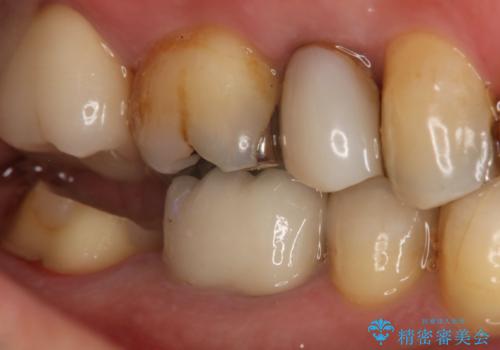

奥歯が痛む オールセラミッククラウン

- 咬んだ時に右下奥歯に痛みがあるとの事で来院された患者様です。

歯の神経は壊死していたため、精密根管治療と補綴治療を計画しました。

セラミックでの治療を希望されたので補綴はオールセラミッククラウンでの治療を選択しました。

痛みは完全に取り除かれ、咬合時の違和感もなく経過は良好です。